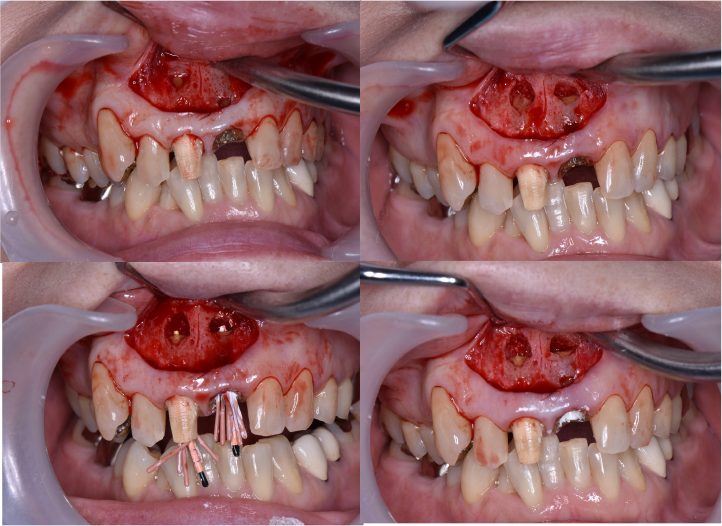

初診時口腔内写真5枚法

初診時口腔内写真五枚法です。

主訴である右上2~左上1は初診日に仮歯に置き換えてあります。

根管治療終了時口腔内写真およびレントゲン写真

根管治療終了時のレントゲン写真及び口腔内写真です。右上1番の根尖病巣の縮小がみられるため、保存可能と判断し矯正治療を行うことにしました。

矯正的挺出終了時の口腔内写真及びデンタル

矯正的挺出終了時の口腔内写真及びデンタル写真です。

レントゲン上で目標とする挺出量がかくとくできたので、この段階で歯周形成外科を行うことにしました。